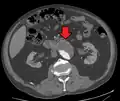

A ruptured AAA with an open arrow marking the aneurysm and the closed arrow marking the free blood in the abdomen -